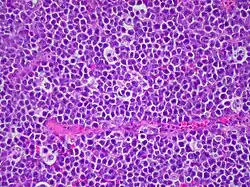

Histologiquement, on décrit ce cancer comme présentant une apparence de « ciel étoilé »[9]. Les cellules lymphoïdes, particulièrement similaires les unes aux autres, s'organisent en couches de cellules ayant de très forts taux de prolifération et d'apoptose.

Ces lymphocytes ont un noyau de forme ronde ou ovale, aux contours réguliers, la chromatine, localisée dans la partie centrale du noyau, se trouvant réticulée avec plusieurs nucléoles de taille ordinaire. Le cytoplasme est basophile à l'examen. Chez les patients immunodéprimés, on peut également découvrir parfois une importante différenciation du cytoplasme avec un noyau à nucléole unique.